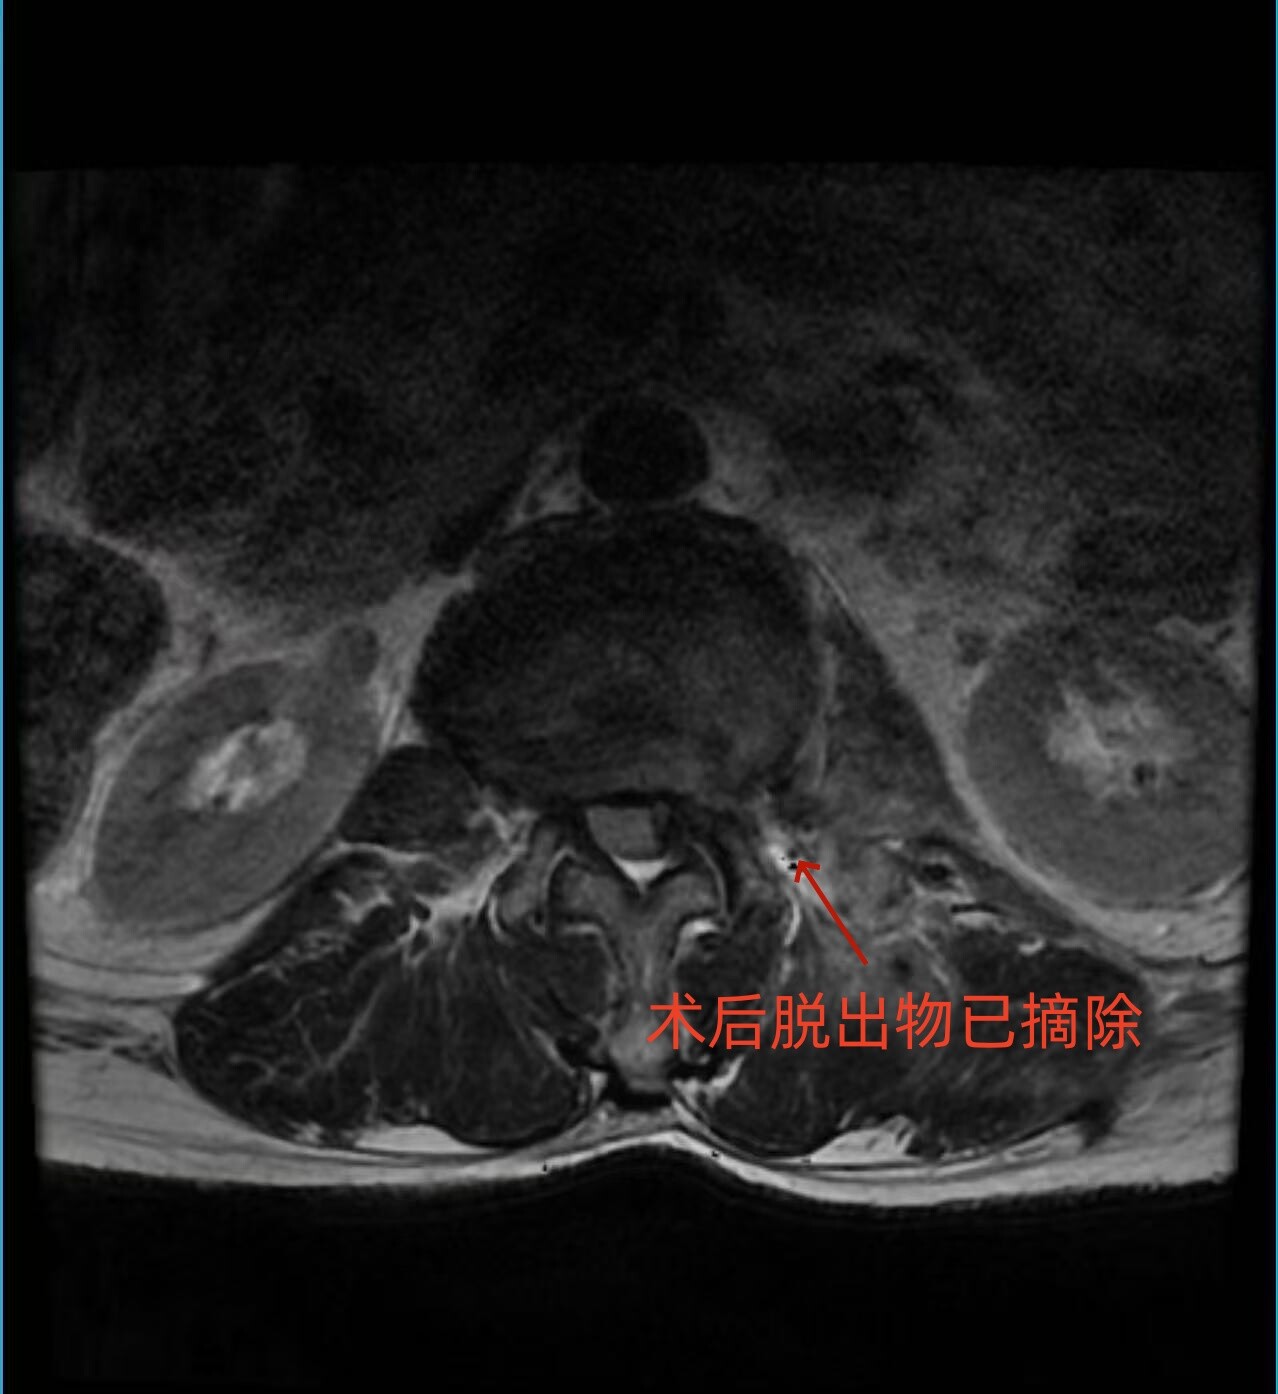

术中,在高清椎间孔镜辅助下,医生精准定位病变节段,小心避开神经根及周围重要组织,逐步剥离并摘除压迫神经的髓核组织。整个手术过程精准、微创、出血少,历时仅1小时,术后伤口仅缝一针。

术后,患者左侧大腿前方的剧烈疼痛完全消失,肢体活动恢复正常。术后第二天,患者即可下地行走自如,精神状态明显好转。复查腰椎MRI显示,压迫神经根的髓核已被彻底摘除,神经根压迫完全解除。